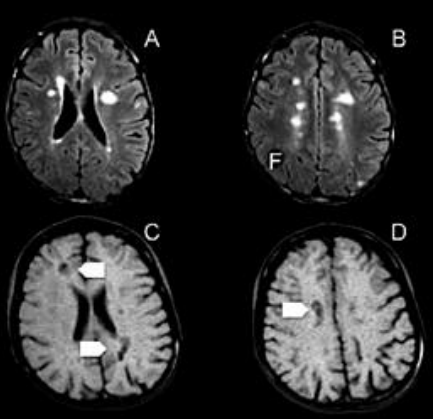

As imagens da ressonância abaixo são sugestivas de:

Provas